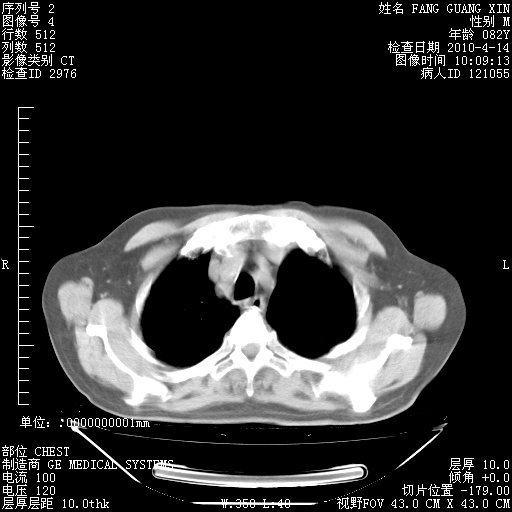

4月14日肺部CT

23.JPG

24.JPG

25.JPG

26.JPG

肺部CT平扫未见异常。